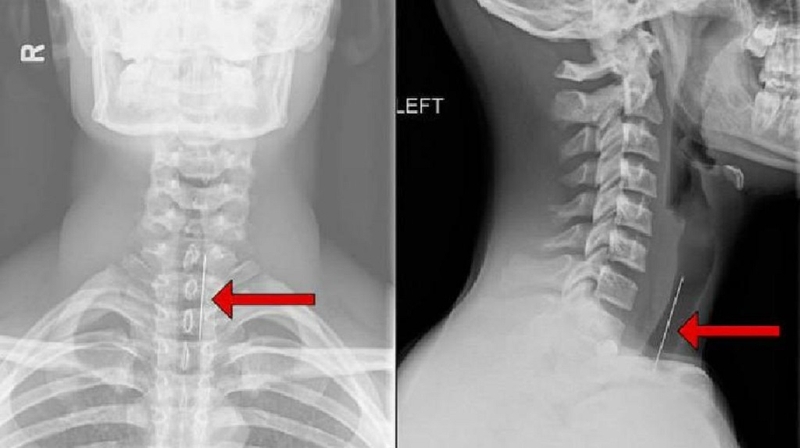

• Chụp X-quang: Được sử dụng để tạo hình ảnh X-ray chi tiết về vùng cổ bên trái, bao gồm cả xương và cấu trúc xương.

Đau cổ bên trái có nguy hiểm không và những cách khắc phục 3

Để chẩn đoán tình trạng đau cổ bên trái, các bác sĩ thường sử dụng các phương pháp chụp X-quang

Dựa trên kết quả của các phương pháp chẩn đoán này, bác sĩ sẽ xác định nguyên nhân cụ thể vì sao cổ bị đau bên trái và đề xuất phương pháp điều trị phù hợp nhất.